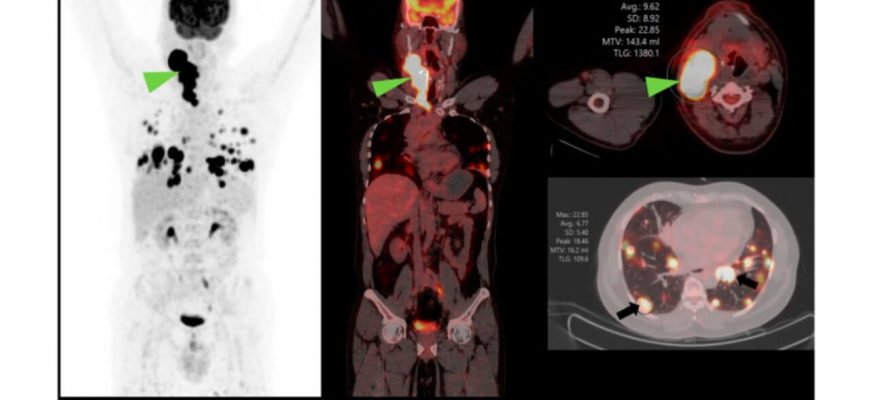

Диагностика рака щитовидной железы с помощью анализа тиреоглобулина: все, что нужно знать Щитовидная железа, один из важнейших органов эндокринной системы